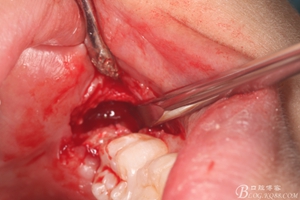

圖15.牙冠完全取出后,用微創(chuàng)丫挺取根

圖16. 38的牙根完整取出,對下頜神經(jīng)管未施加壓力

圖17. 縫合